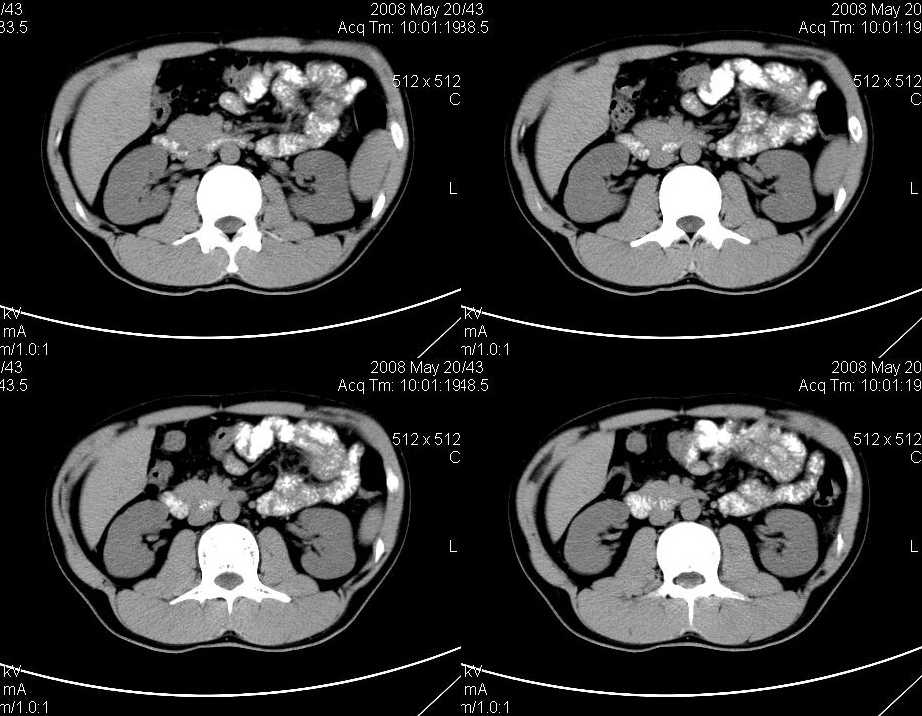

以下是引用liuyue在2008-6-7 15:28:00的发言:[br]典型的:肾癌。[br]动脉期强化明显,而静脉期密度明显降低,呈低密度。